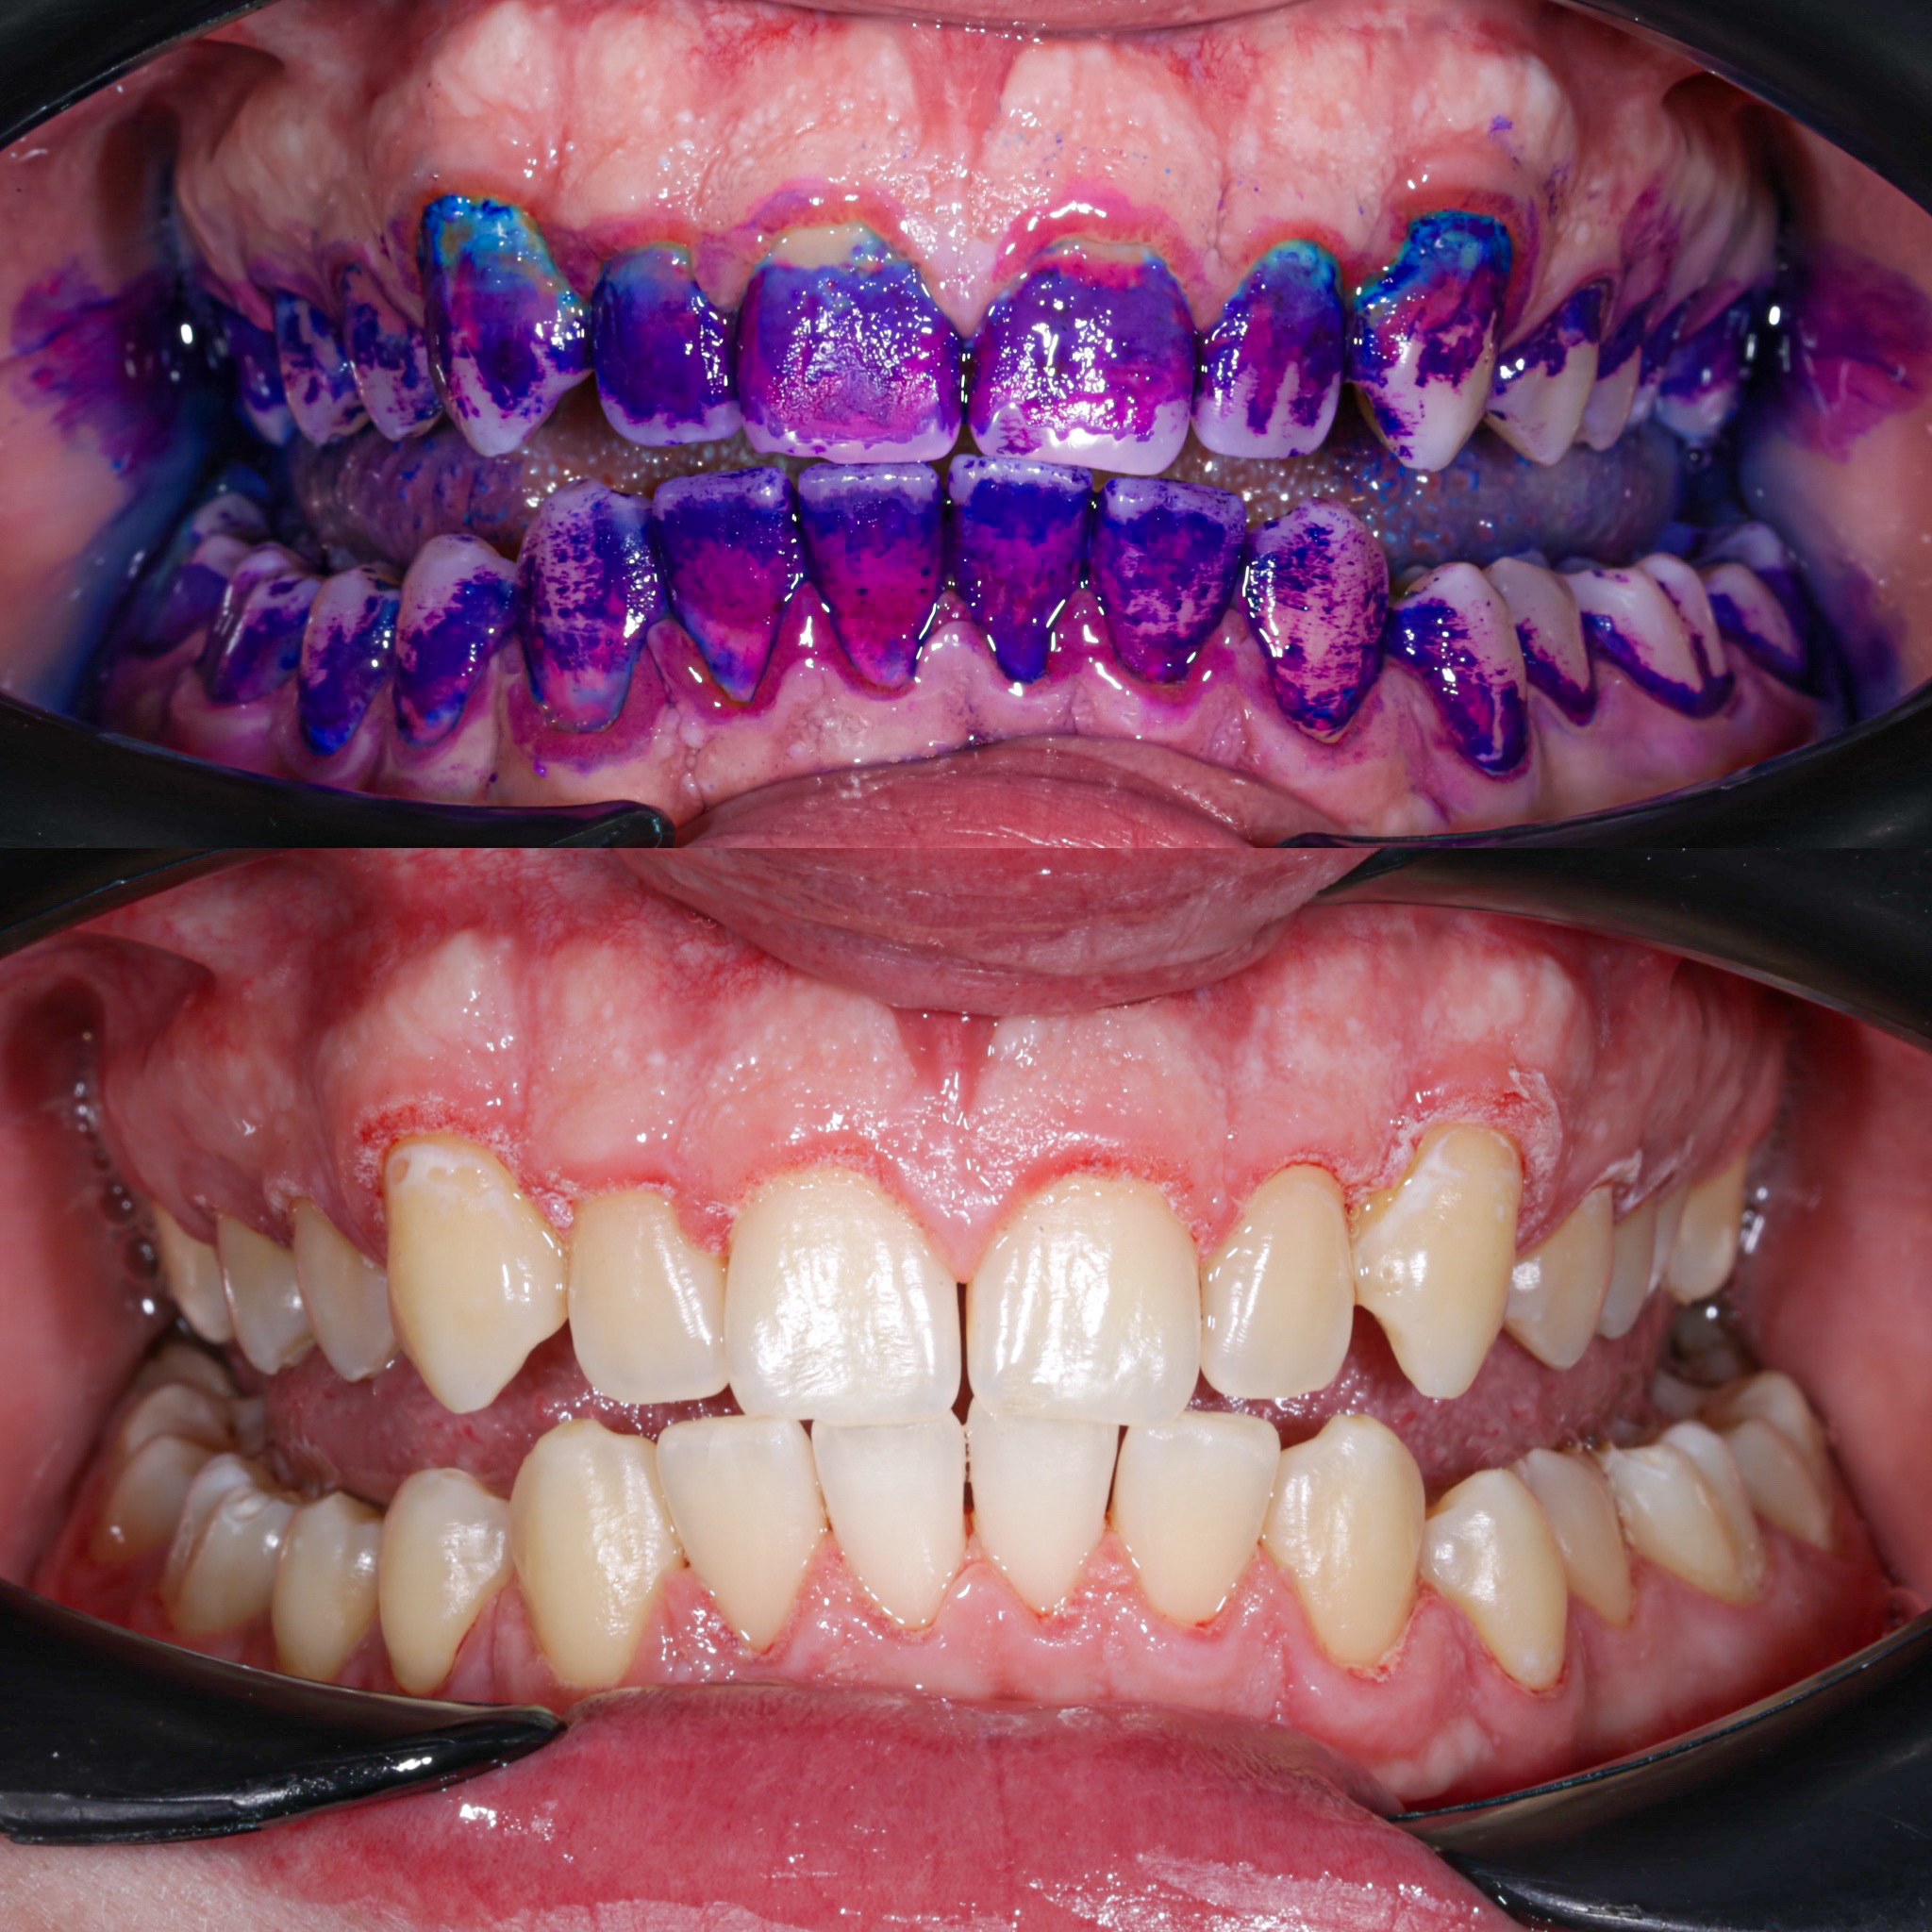

- визначення гігієнічого індексу

- скринінг тест ясен на визначення прихованих захворювань

Галерея

Професійна гігієна (чистка) зубів складається з кількох етапів

• Комп'ютерна анестезія у разі підвищеної чутливості зубів.

• Зняття каменю ультразвуковим девайсом SIRONA (Німеччина) та звуковим наконечником KAVO (Німеччина) з електронним регулюванням потужності.

• Зняття каменю у важкодоступних місцях пародонтальними кюретами HU-Friedy.

• Зняття нальоту гігієнічними перлинами KaVo PROPHY pearls SUPRAGINGIVAL CALCIUM CARBONATE в індивідуальних пакуваннях із ароматом на вибір: персик, апельсин, м'ята, чорна смородина та нейтральний смак.

• Полірування швейцарською пастою Proxyt Ivoclar Vivadent для блиску та природної білизни.

• Діагностика прихованих захворювань ясен (скрінінг-тест).